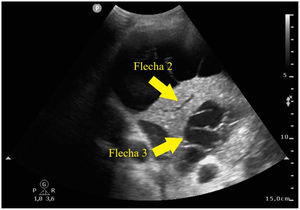

Paciente de 52 años con antecedente personal de síndrome de inmunodeficiencia adquirida, que ingresa en nuestra unidad por neumonía adquirida en la comunidad por Streptococcus pneumoniae. En la radiografía de tórax se objetiva infiltrado basal derecho y se realiza tomografía computarizada de tórax con hallazgos de neumonía necrotizante con probable absceso pulmonar incipiente. Presenta mala evolución, con hipoxemia refractaria a ciclos de prono, realizándose ecografía pulmonar. Se observa derrame pleural con trayectos fibrosos hiperecogénicos o signo del plancton en su interior (fig. 1, flecha 1), infiltrado basal derecho con hiperecogenicidad del parénquima por hepatización del mismo con broncograma aéreo, también interno (fig. 2, flecha 2), así como zonas trabeculadas hipoecogénicas bien delimitadas, compatible con neumonía necrotizante y absceso pulmonar (fig. 2, flecha 3).